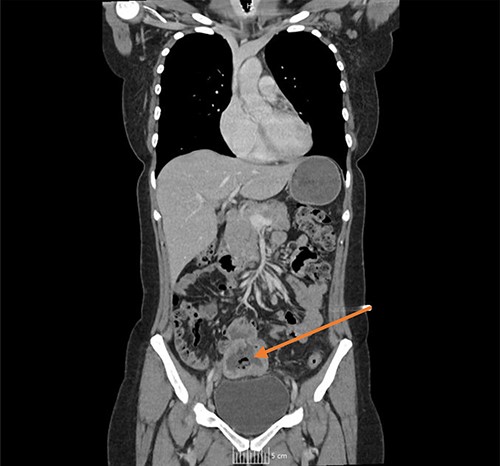

Once admitted to the haematology department, she was examined and was found to have a soft, non-tender abdomen with no signs of peritonism, and all her other systemic examinations were normal. Given the vague abdominal symptoms and blood profile, she was subjected to a CT scan of her chest, abdomen and pelvis (CT CAP). The scan reported a lower abdominal/pelvic thick-walled fluid and gas-filled structure that measured 5 × 7 × 6 cm lying adjacent to the urinary bladder with a likely fistulous tract to the overlying loops of bowel. A small amount of free fluid and non-specific stranding of fat was seen in the pelvis. No pulmonary or metastatic nodules were seen (Figs 1 and 2).

CT coronal image, with arrow showing the midline lower abdominal/pelvic thick walled fluid and gas-filled structure that measured 5 × 7 × 6 cm.